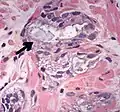

Glomerulation.

- Collagenous micronodules[4]

- Glomerulations,[4] epithelial proliferations into one or more gland lumina, typically a cribriform tuft with a single attachment to the gland wall.[18]